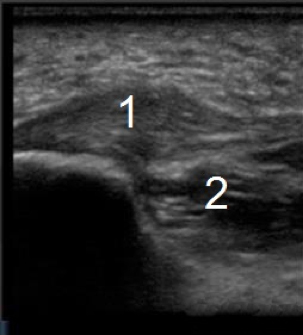

Foot & Ankle Normal Plantar Image

Plantar Fascia

Inferior Margin